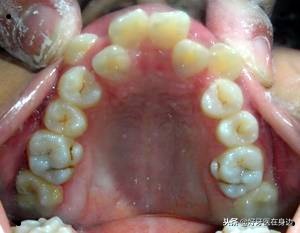

“双排牙”有什么危害?

“双排牙”出现后卫生很难清洁,容易嵌塞食物,导致龋齿的发生,另外一个最重要的影响就是牙齿不齐,牙齿错颌畸形以及面部畸形!

牙齿不齐